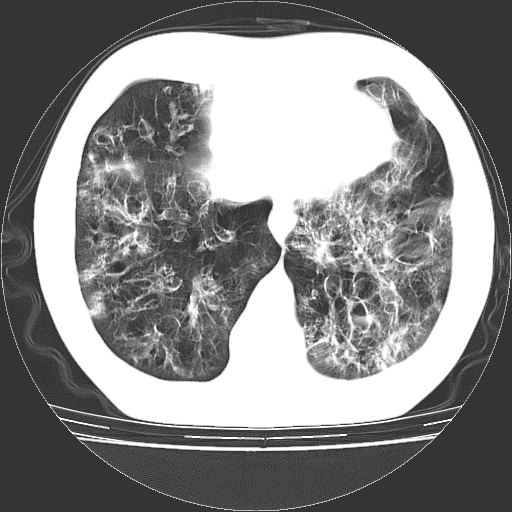

以下是引用zyx168在2006-12-4 15:30:00的发言:[br]经典!支气管肺囊肿并感染。

以下是引用dyqct在2006-12-4 17:11:00的发言:[br]典型的囊状支扩合并感染。

以下是引用liaoqiang在2006-12-4 16:12:00的发言:[br]局部肺叶内可见扩张的支气管壁,考虑为支扩。部份囊样影内有小液平和肺内散布斑片征影、小结节及纤维灶,提示支扩伴感染,且由于局部呈现有树芽征感染以结核可能性大。

以下是引用zhoucan076在2006-12-4 16:48:00的发言:[br]囊状支扩合并感染